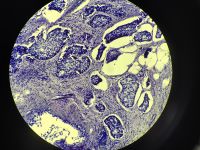

乳腺小叶癌?

性别

女

年龄

49

临床诊断

乳腺肿物

一般病史

肿物半年

标本名称

大体所见

直径2.8

浸润性癌 鉴别微乳头状癌

考虑:符合浸润性

小叶癌

考虑 浸润性导管癌,3级,8分。